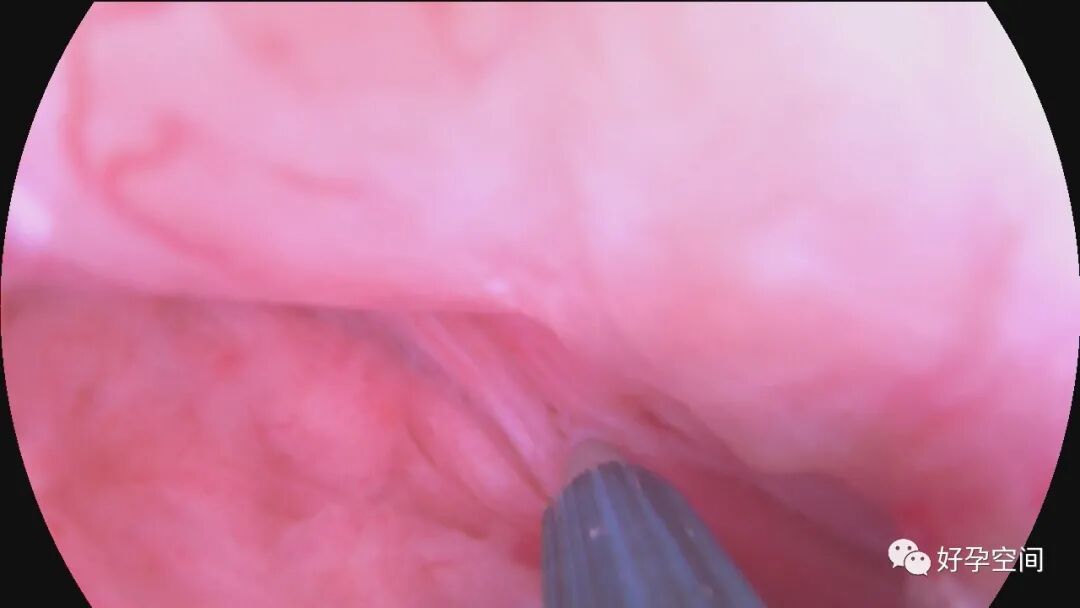

病例1:61岁,G2P1,剖宫产1次,原发性高血压。安环28年,绝经3年。病人肥胖,身高156cm,体重85kg。阴道深,一次性扩阴器勉强暴露宫颈,宫颈萎缩,宫颈钳很难夹持住,反复松脱,置入一次性宫腔镜见节育环坎顿,异物钳艰难取出节育环,偶然见宫腔下段后壁息肉,约1.5cm*1.0cm*0.8cm,异物钳从根部摘除息肉。